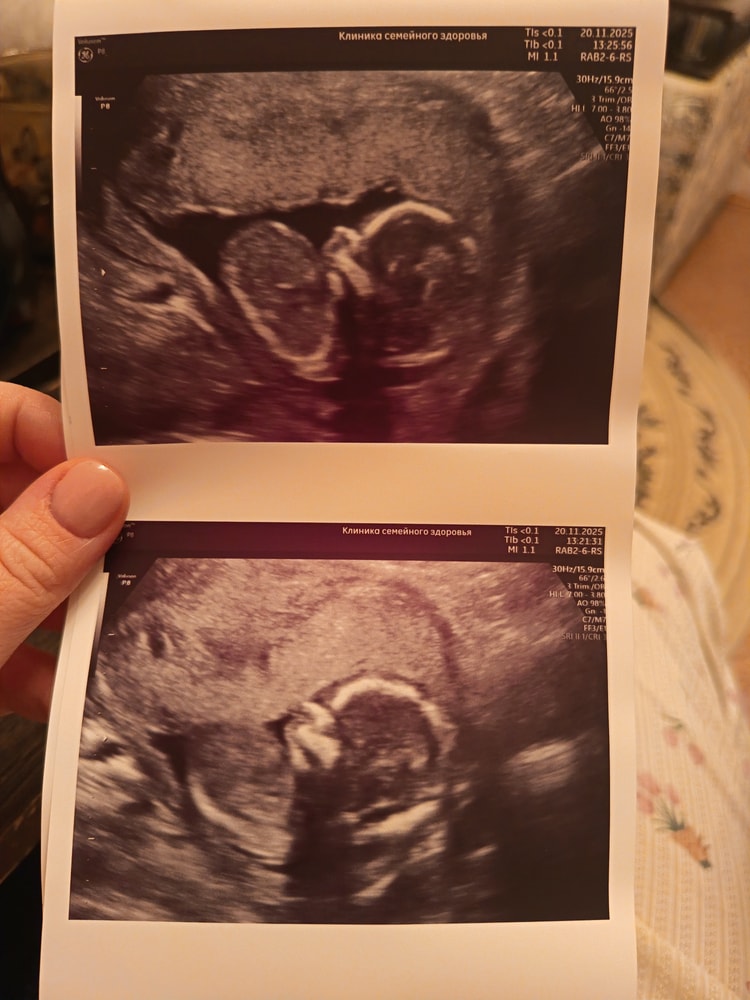

20.11 была на УЗИ, врач всё посмотрела, сказала отлично, малыш растёт. Пол врач увидела, но как мы с мужем и решили, будем делать гендер пати когда он приедет с вахты в середине декабря, эх терпения мне🤭😁уже не терпится узнать кто же там в животике живёт 😍 на УЗИ малыш как врач сказала с характером, даже не получилось сделать красивые снимки, лежит не удобно, но как по мне, эти даже ещё лучше🥰💗 сначала спал, мы его пока делали УЗИ разбудили, малыш стал кулаки показывать, попу, а в конце вообще спиной развернулся😁🤭 на секунду даже показалось что мальчишка😊 по весу написали 118 +/- грамм счастья😍 девушки, у кого примерно такой же срок, как у вас дела, как самочувствие? 😊